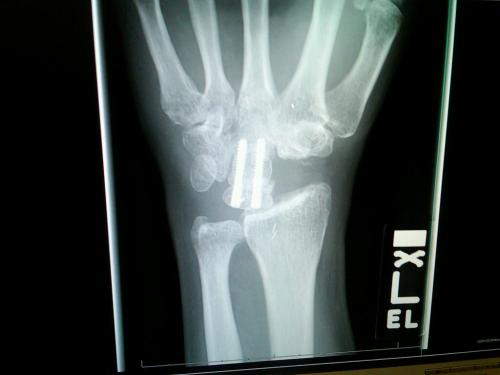

Remember change one up above? The arthritis? When you combine poor boxing form and years of arthritic erosion in small joints, you get two wrists that look like this:

Given that most of us are not clinically trained in hand and wrist anatomy and physiology, here’s what my orthopedic surgeon said this past fall when he saw that X-Ray. He dumbed it down for me. He said this. “Ummmm, all your bones on the bottom are in the wrong places. We should fix that. That looks like it might hurt.”

And, it did. My hands have hurt every minute of every day for the last two years with the last three months being the most painful. The good pain, though…the kind that lets you know you’re alive and wakes you up in day long meetings.

This morning, as you are reading this, my wonderfully skilled surgeon at Scripps Green is removing some of those messed up bones in one of the wrists, pulling the remaining bones together with K-wires, plates and screws and then using an iliac crest graft from my hip as the frosting on top of his four corner fusion on the left wrist. He is going to do this: